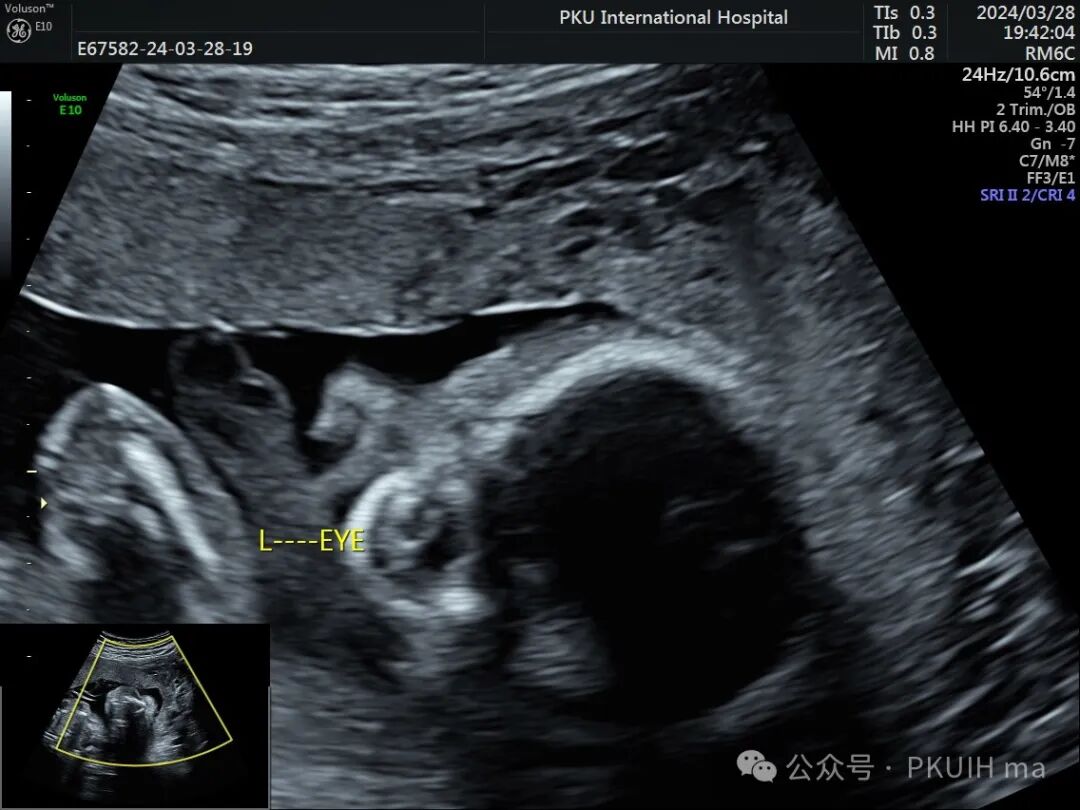

左眼发育大小正常,但晶状体边缘增厚回声也增高,应该也是有问题

右眼球情况:两个手标分别代表晶状体和后方的永存玻璃体

实时动态观察双眼发育不对称,右眼小;两侧眼球内晶状体、玻璃体均可见,右侧晶状体小,晶状体后缘玻璃体内见不规则的高回声区。

PHPV的超声表现:一侧眼球晶状体后方可见Y形高回声或强回声条带,或者是晶状体后方圆形或圆弧状高回声团块(直接征象);同时伴有患侧眼球小,晶状体形态异常,眼轴短,部分有玻璃体浑浊。双眼发病极为罕见,表现双层晶状体浑浊,内见不规则强回声或高回声带。CDFI:部分病例可见增生的玻璃体动脉内见血流信号。该病容易反复发生眼内出血,纤维血管性肿块的收缩可能对视网膜产生牵拉,导致视网膜脱离。因此,眼部超声表现可能会随着妊娠进展而改变。